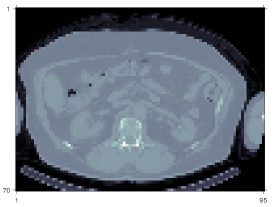

Fig. 2 compared the primary projections generated by different methods without adding Poisson noise. Visualizations of image slices and line profiles illustrate that our Julia projector (with rotation based on 3-pass 1D interpolation) is almost identical to the Matlab projector, while both give a reasonably good approximation to the MC. Using MC as reference, the NRMSE of Julia1D/Matlab/Julia2D projectors were 7.9%/7.9%/7.6% for Lu177superscriptLu177{}^{177}\mathrm{Lu}, respectively; while the NRMSE were 8.2%/8.2%/7.9% for Y90superscriptY90{}^{90}\mathrm{Y}. We also compared the OSEM reconstructed images using Julia (2D) and Matlab projectors, where we did not observe notable difference, as shown in Fig. 3. The overall NRMSD between Matlab and Julia (2D) projector for the whole 3D OSEM reconstructed image ranged from 2.5% to 2.8% across 3 noise realizations.

Figure 3: Comparison of one slice of the 128×128×8012812880128\times 128\times 80 OSEM reconstruction (16 iterations, 4 subsets) using Matlab and Julia (2D interpolation) projectors.